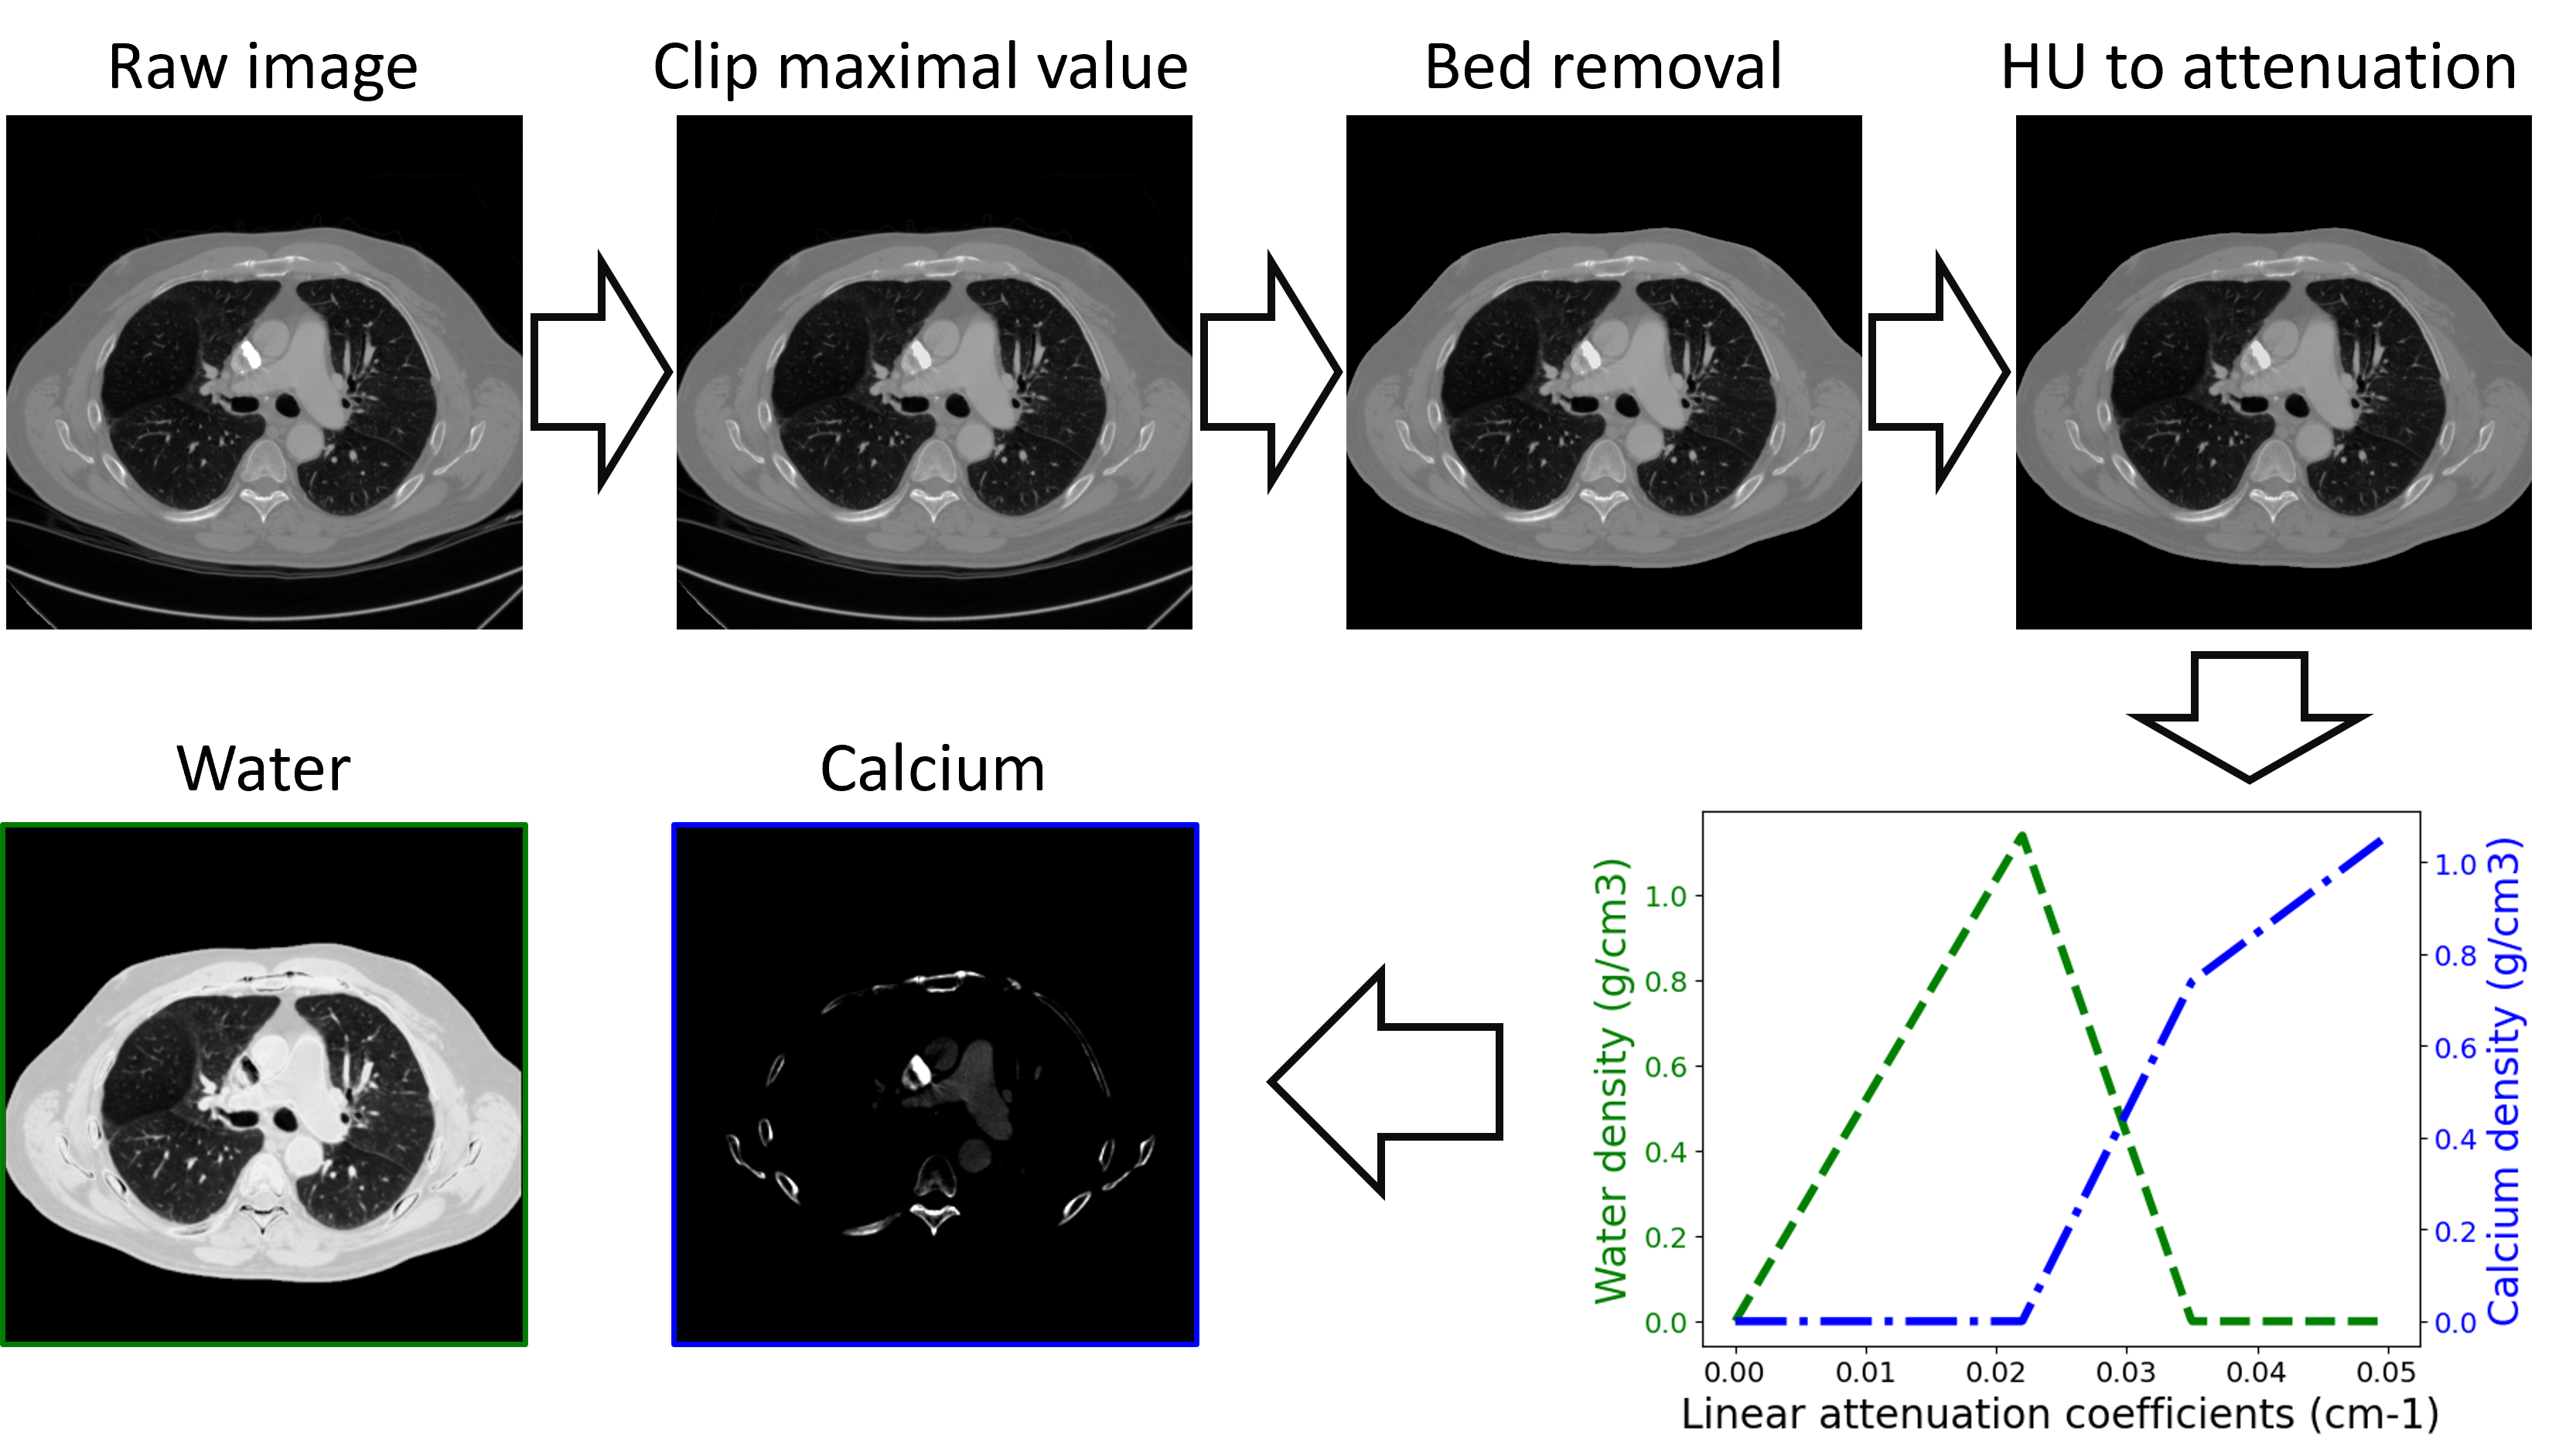

The dataset generation procedure is summarized in Fig.2. We investigated water/calcium decomposition in this work. A two-material dataset was created based on the public CT Lymph Nodes dataset[39], from which chest-region slices were extracted from 150 distinct patients, forming a CT dataset of 30000 slices. Pre-processing includes bed removal via morphological operations and metal reduction via clipping the maximum value to 2000HU. Hounsfield unit values were converted into attenuation coefficients, and then water and calcium densities (unit: g/cm3𝑔𝑐superscript𝑚3g/cm^{3}) were determined by two soft-threshold functions:

Refer to caption

Figure 2: Summary of the processing used to create the two-material dataset from public single-energy CT images.

xw(μ)={kwμ,if μμwkwμwkwc(μμw),if μw<μ<μc0,otherwisesubscript𝑥𝑤𝜇casessubscript𝑘𝑤𝜇if 𝜇subscript𝜇𝑤subscript𝑘𝑤subscript𝜇𝑤subscript𝑘𝑤𝑐𝜇subscript𝜇𝑤if subscript𝜇𝑤𝜇subscript𝜇𝑐0otherwisex_{w}(\mu)=\begin{cases}k_{w}\mu,&\text{if }\mu\leq\mu_{w}\\ k_{w}\mu_{w}-k_{wc}(\mu-\mu_{w}),&\text{if }\mu_{w}<\mu<\mu_{c}\\ 0,&\text{otherwise}\end{cases} (10a)

xc(μ)={kc(μμc)+kcw(μcμw),if μμckcw(μμw),if μw<μ<μc0,otherwisesubscript𝑥𝑐𝜇casessubscript𝑘𝑐𝜇subscript𝜇𝑐subscript𝑘𝑐𝑤subscript𝜇𝑐subscript𝜇𝑤if 𝜇subscript𝜇𝑐subscript𝑘𝑐𝑤𝜇subscript𝜇𝑤if subscript𝜇𝑤𝜇subscript𝜇𝑐0otherwisex_{c}(\mu)=\begin{cases}k_{c}(\mu-\mu_{c})+k_{cw}(\mu_{c}-\mu_{w}),&\text{if }\mu\geq\mu_{c}\\ k_{cw}(\mu-\mu_{w}),&\text{if }\mu_{w}<\mu<\mu_{c}\\ 0,&\text{otherwise}\end{cases} (10b)

The parameters, kwsubscript𝑘𝑤k_{w}, kwcsubscript𝑘𝑤𝑐k_{wc}, kcwsubscript𝑘𝑐𝑤k_{cw}, kcsubscript𝑘𝑐k_{c} were empirically set to 5.185.185.18, 8.778.77-8.77, 5.695.695.69, 2.12g/cm22.12𝑔𝑐superscript𝑚22.12~{}g/cm^{2}, while μwsubscript𝜇𝑤\mu_{w} and μcsubscript𝜇𝑐\mu_{c} were 0.22cm10.22𝑐superscript𝑚10.22~{}cm^{-1} and 0.35cm10.35𝑐superscript𝑚10.35~{}cm^{-1}. Fig.3 illustrates example images in the synthetic two-material dataset. Part of the soft tissue, notably in the heart region, exhibits high intensity in the calcium images because of iodine contrast enhancement.